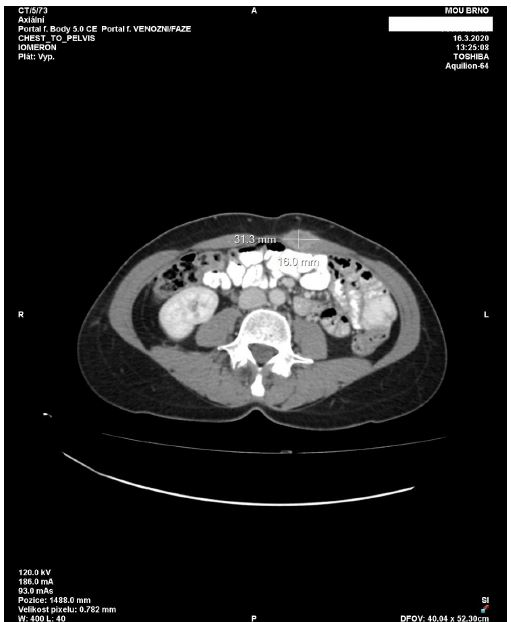

Further elevation of serum tumour markers - CEA and CA 19-9 - was noticed in March 2020. The CT scan of the thorax and abdomen revealed a small lesion in the abdominal wall, measuring approximately 3 cm in diameter. No additional pathology was identified on the CT scan. The colorectal MDT recommended surgical resection of the suspicious abdominal wall lesion with reconstruction of the abdominal wall. The surgery was performed on 29 April 2020. The abdominal wall was resected in full thickness and substituted with Vicryl and Prolene meshes. No signs of pathology in the abdominal cavity were found. The patient was discharged on the fifth postoperative day. Histopathologic examination of the specimen revealed metastatic adenocarcinoma of colorectal origin (Figure 1d), and R0 resection was performed. Medical oncologists suggested follow-up without any adjuvant treatment, and the patient agreed. In January 2025, the patient returned to our clinic for a follow-up. The patient was fit and well without any signs of cancer recurrence.

Figure 5: Scan detected a new tumour lesion measuring 31×16 mm located in the abdominal wall in the medial border of the left rectus abdominis muscle.

The suggested metastases are indicated with arrows and the serosal surface with arrowheads.